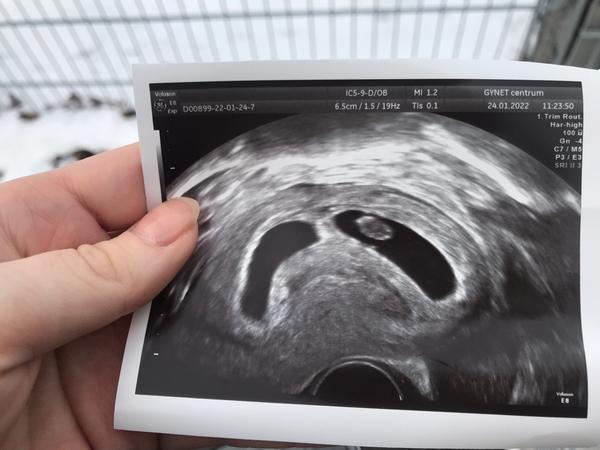

Ahoj holky, jdu se tady k vám přidat, momentálně jsem 7+4tt s dvojčátky. Zvládli jsme dvou týdenní krvácení z hematomu a v pondělí jsem byla naposled na kontrole a bobišci jsou oba stejně velcí a hezky jim bijí srdíčka 🥰 jsem od 5+5tt na nemocenské, kvůli predeslym potratum a tomu krvácení 🙂 na fotku se vždy jeden schoval 🥰